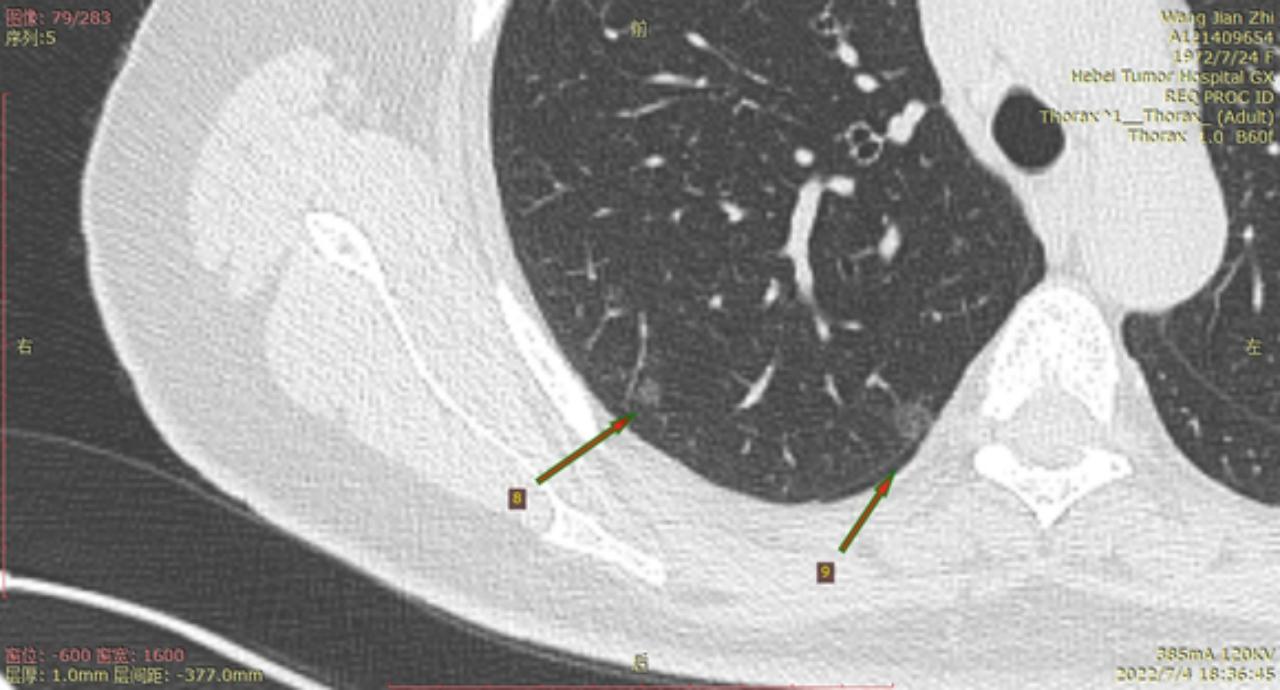

结8-11